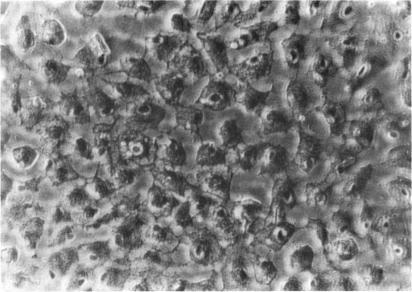

Three major pathologic processes caused by light in the primate retina: a search for mechanisms.

Trans Am Ophthalmol Soc. 1982;80:517-79.